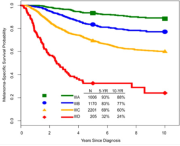

| 08:03, 4 בנובמבר 2023 | AJCC8-5.png (קובץ) |  |

514 קילו־בייטים | Motyk | 1 | |